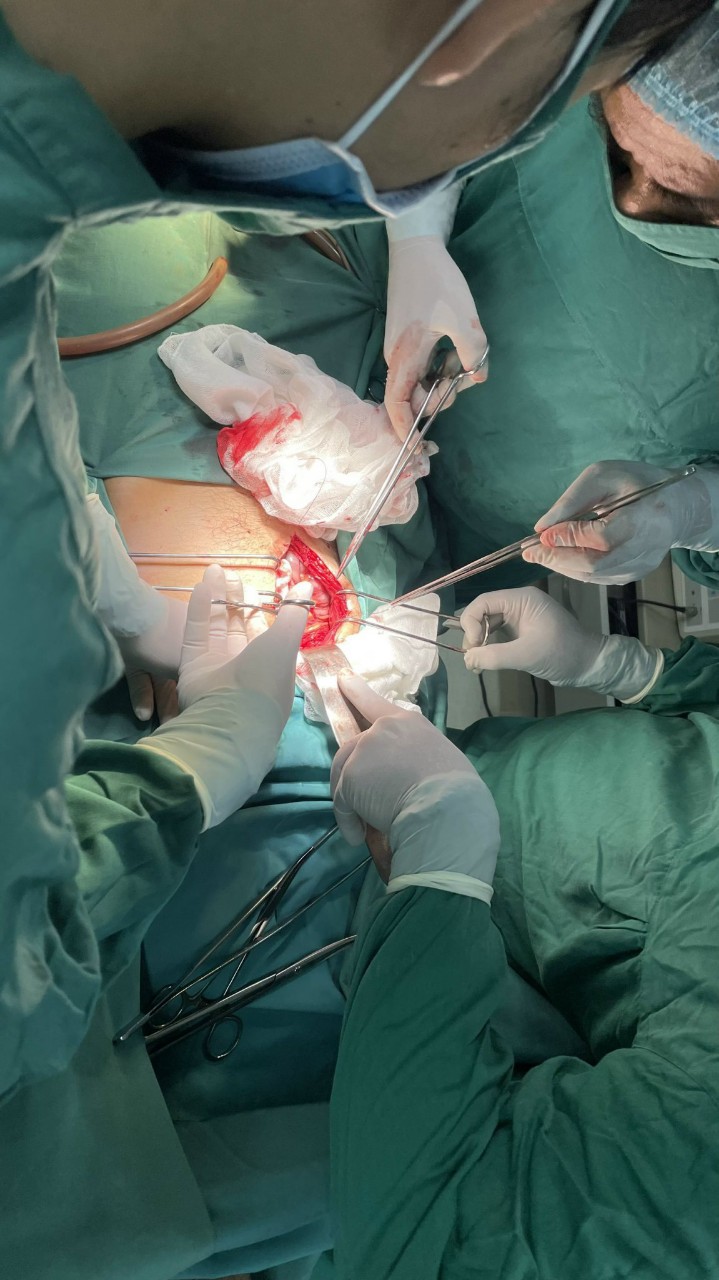

Dị vật là cây sắt kích thước 40cm x1cmCác Bác sỹ khoa ngoại đã tiến hành hội chẩn với khoa Gây mê- Hồi sức tiến hành phẫu thuật cấp cứu. Trong mổ, kiểm soát các tổn thương phát hiện dị vật đâm thủng thành sau phúc mạc, gây rách mạc treo đại tràng ngang, rách phúc mạc thành sau, gây vết thương tổn thương cực trên thận. Trong quá trình phẫu thuật đã lấy ra dị vật là cây sắt kích thước 40cm x1cm, khâu vết thương thận, cầm máu mạc treo.

Các Bác sỹ khoa ngoại đã tiến hành hội chẩn với khoa Gây mê - Hồi sức tiến hành phẫu thuật cấp cứu